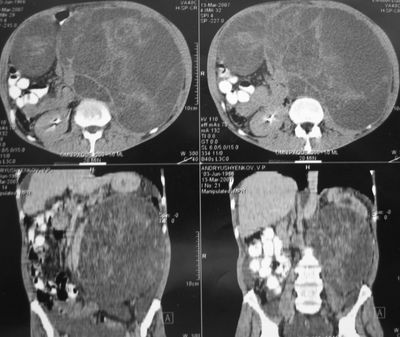

Метастаз в забрюшинный лимфоузел